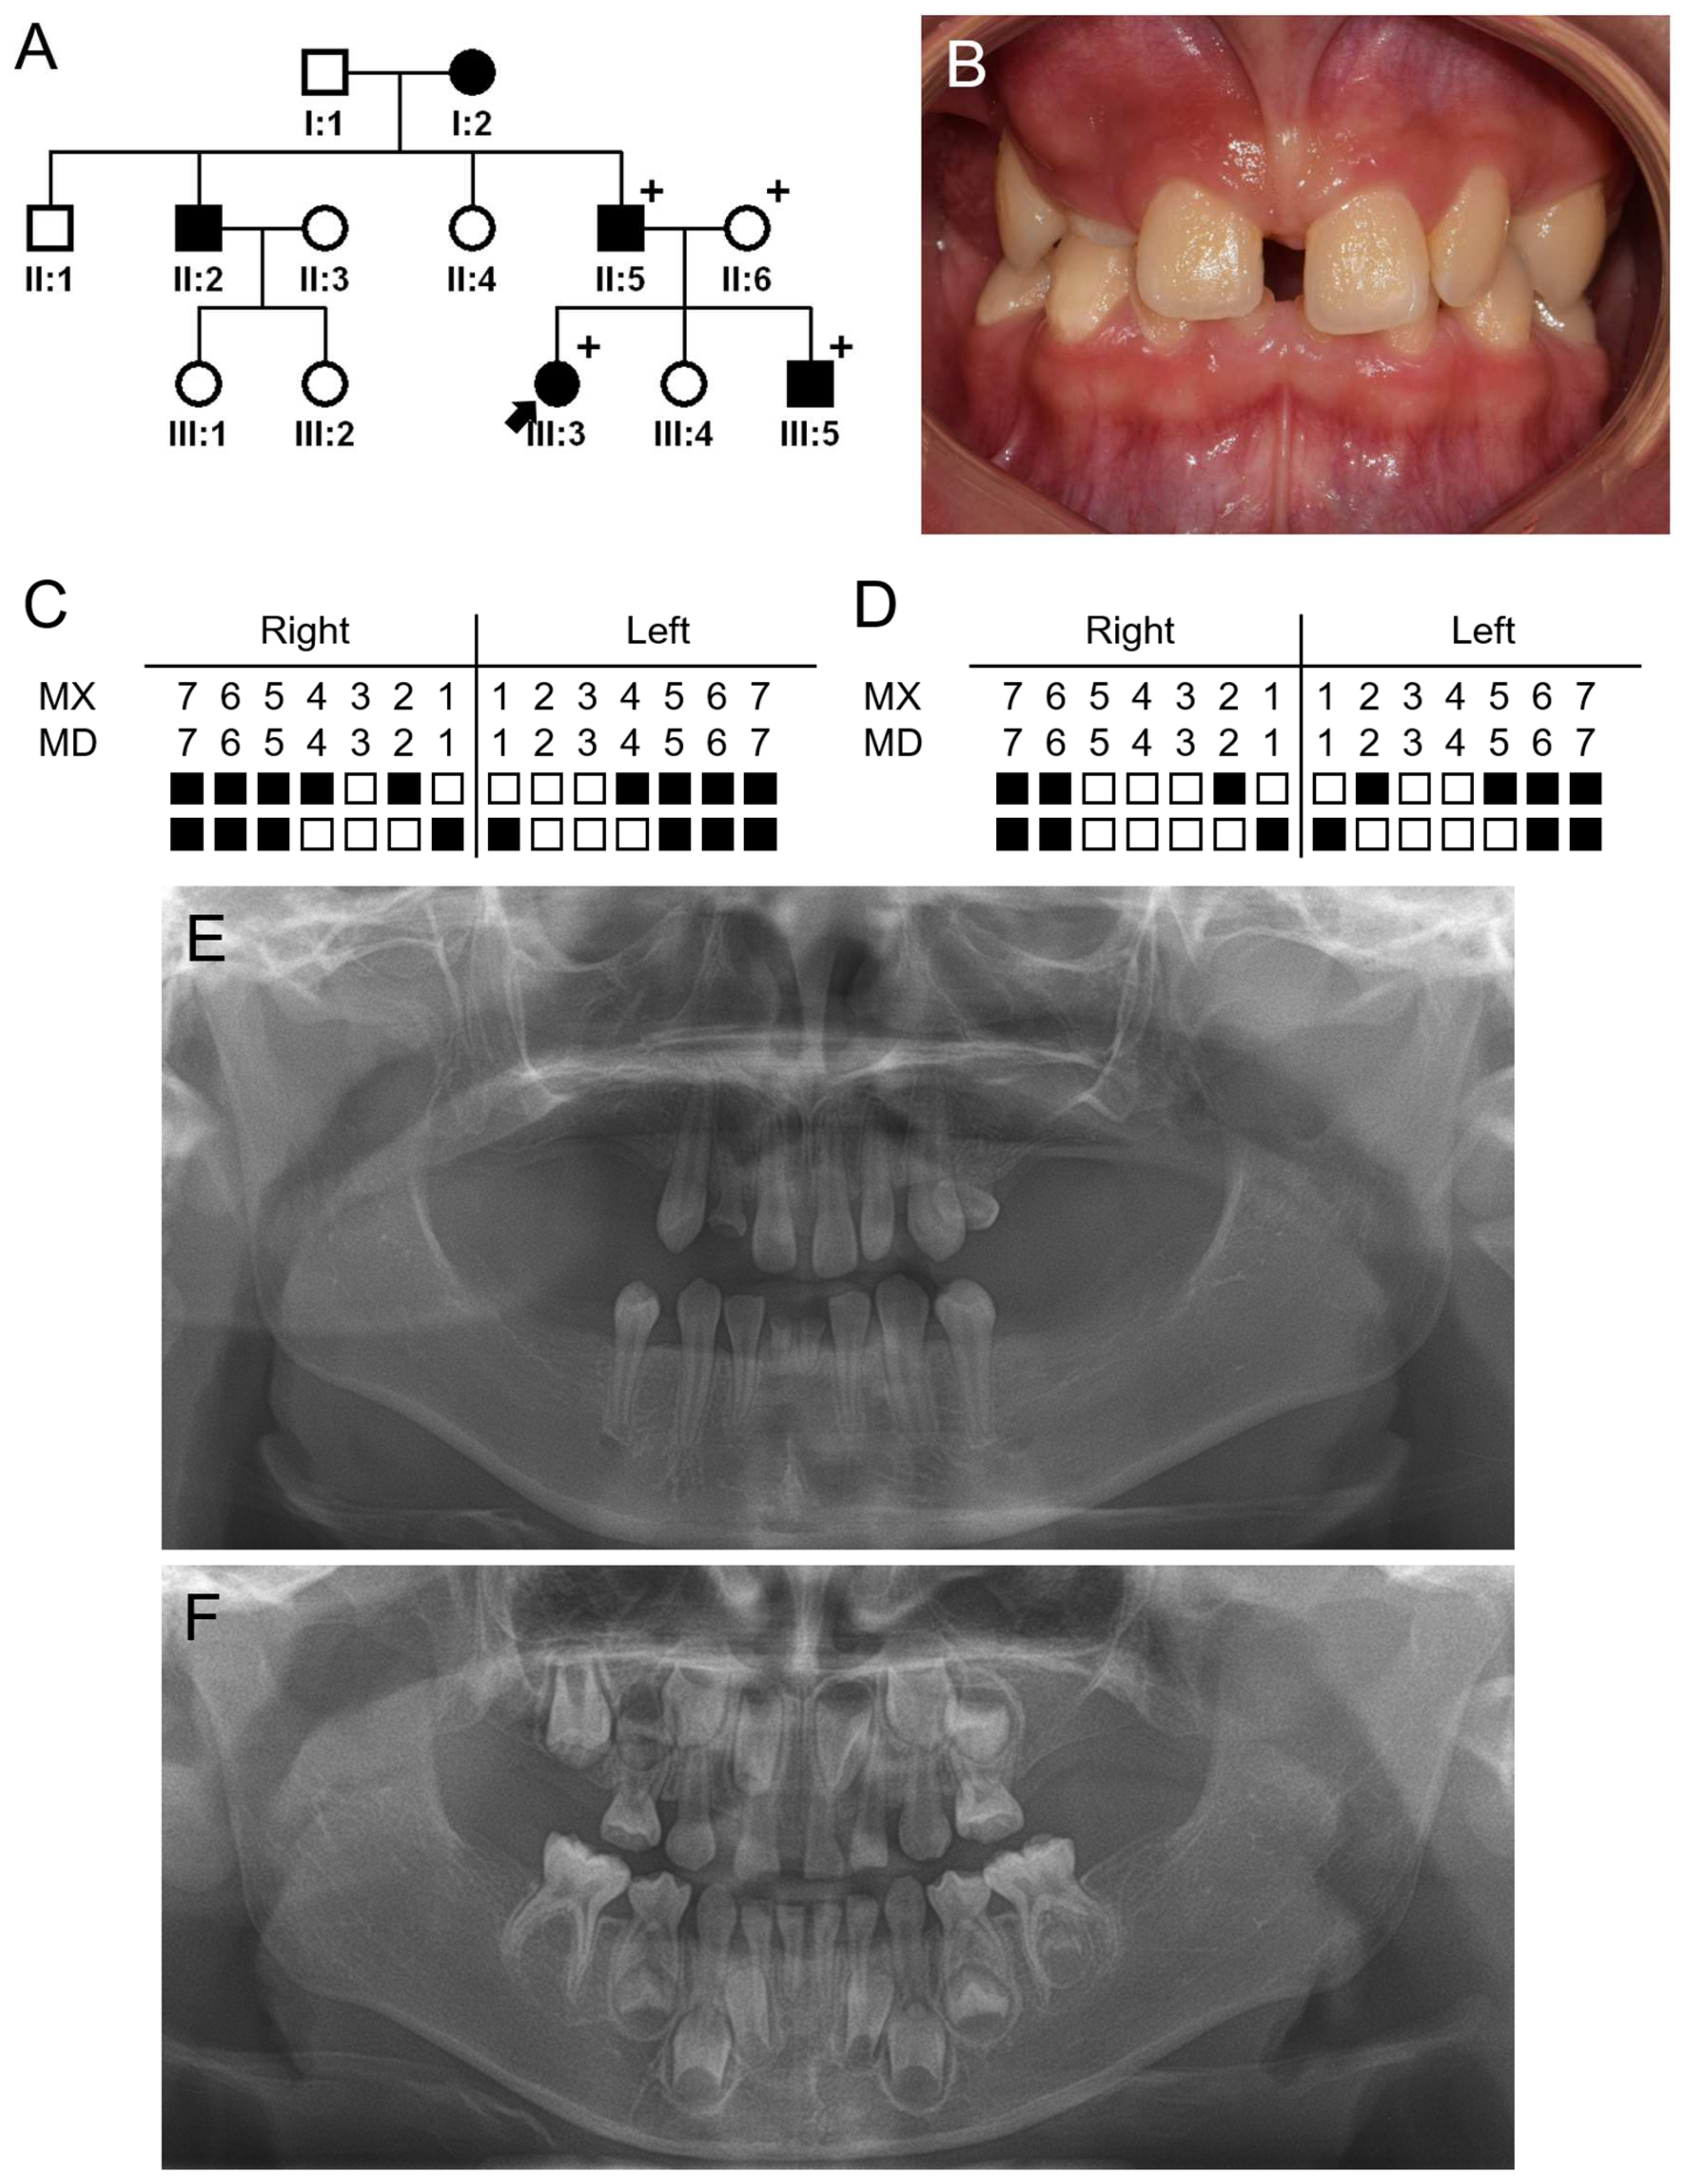

3.1. Family 1

3.2. Family 2